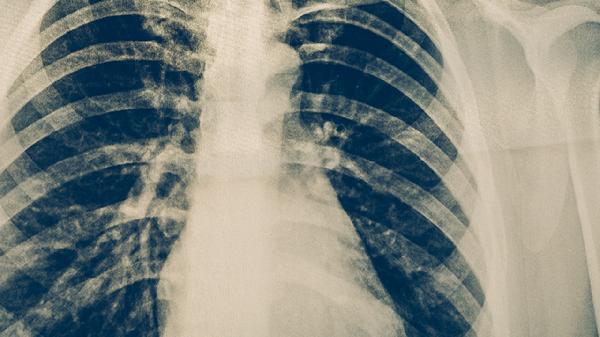

胸部X線可顯示肺結(jié)核特征性病變,如上肺野浸潤(rùn)影、空洞形成或纖維鈣化灶。典型影像學(xué)表現(xiàn)結(jié)合臨床癥狀可初步診斷,但需注意與其他肺部疾病鑒別。對(duì)于疑似病例,可能需進(jìn)一步行胸部CT檢查評(píng)估病變細(xì)節(jié)。